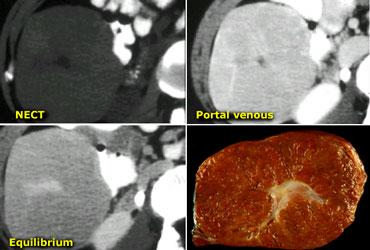

NECT, arterial and portal venous phase in a patient with Hepatitis C with two lesions in the liver (arrows).

Trong thì động mạch, chúng ta thấy hai tổn thương tăng sinh mạch.

Các hình ảnh phía trên cho thấy một tổn thương đồng tỷ trọng với gan trên CCLVT không tiêm thuốc.

Trong thì động mạch có sự ngấm thuốc, nhưng không đậm bằng tỷ trọng máu trong lòng mạch.

Trong thì tĩnh mạch cửa, tổn thương lại đồng tỷ trọng với nhu mô gan xung quanh và không thể nhìn thấy.

Nếu chỉ có thì tĩnh mạch cửa, chắc chắn bạn sẽ bỏ sót tổn thương này.

Các hình ảnh phía dưới cho thấy một tổn thương có thể nhìn thấy trên tất cả các hình ảnh.

Bạn thấy nó trên CCLVT không tiêm thuốc và có thể nhận xét rằng nó giảm tỷ trọng so với gan.

Tuy nhiên, nếu nhìn vào tỷ trọng máu trong lòng mạch, bạn sẽ nhận thấy rằng ở tất cả các thì, tổn thương có tỷ trọng tương đương với máu trong lòng mạch.

Vậy chúng ta có một ung thư biểu mô tế bào gan ở thùy phải trên các hình ảnh phía trên và một u máu ở thùy trái trên các hình ảnh phía dưới.

Điều quan trọng là phải xem xét tất cả các thì chụp.